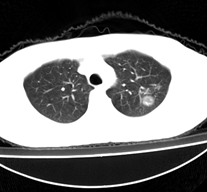

病人为一考上研究生的学生,健康体检发现。请踊跃发表意见。

左肺上叶见后段近侧胸壁见两个薄壁空洞影,洞内无液平,考虑肺囊肿,因为肺囊肿位于肺的外周,囊肿与支气管相通,囊壁薄,囊内无液性成分。以上使我的观点,原与各位交流

左肺上叶尖后段胸膜下可见两个类圆形薄壁空洞,内外壁较光滑,腔内为气体密度,支持结核性薄壁空洞。

我想应是肺囊肿,因为边界清晰,其内无液平面,周边没有卫星灶,还有临床也不支持肺结核

临床无症状,左上肺两枚厚壁空洞,内无气液平面,周围未见卫星灶,囊肿可能大,建议追问病史。请各位老师指正

左飞上叶尖后段两个含气的囊性肿块,边界清晰,其周围未见卫星病灶,考虑肺囊肿.不支持肺结核是因为未见卫星灶,临床未见体征.

左肺上叶后段见两个孤立圆形厚壁空洞,无液平及壁结节。周围清晰,无卫星灶。结合病史,如此大的病灶病人毫无感觉,另外周围如此清晰,应能排除结核空洞;肺囊肿壁应更薄,如合并感染可增厚,但周围应模糊。本人考虑:肺韦格肉芽肿。

左肺上叶后段见两个孤立圆形厚壁空洞,无液平及壁结节。周围清晰,无卫星灶。结合病史,如此的病灶病人毫无感觉.考虑1肺部感染[注意新隐球菌感染----中华放射学杂志---2006----第一期-----104页]。2肺囊肿。请指教!!!

左上叶尖后段可见两个中等壁厚空洞,腔内无液平,内外壁光整,局部轻度胸膜增厚,首虑结核。

考虑肺囊肿可能性大。不支持结核是因为周围肺野内未见明显卫星灶及纤维索条,不支持韦格氏肉芽肿是因为内壁及外壁均很光整,壁厚薄一致,而韦格氏肉芽肿洞壁厚薄多不均匀,内壁多不规则,其内可有形态不规则的内容物。

左肺尖后段的两个薄壁(纵隔窗)含气囊样病变,壁厚薄较均匀、光整、内无液气平形成、其邻近肺野见

少许渗出、未见卫星灶,其余肺野未见明显支气管播散灶(楼主虽然未上传全其他层面图片,但认为因正常而未上传)。

综合上述:考虑为肺囊肿合并感染,不支持结核空洞(虽然病变位于结核好发区,但认为这么明显的结核空洞应该有明显的肺内支气管播散灶)。